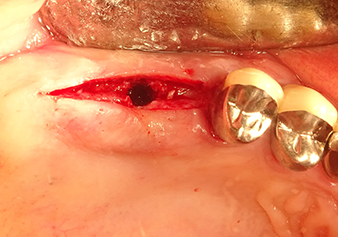

Preparazione e accrescimento della sede dell'impianto

Dopo un controllo intermedio (Fig. 4) è stata eseguita un'ulteriore fase di preparazione (Fig. 5). Lo strumento idraulico Z35P è stato utilizzato in un secondo momento per sollevare la membrana sino alla posizione desiderata (Fig. 6 e 7). In seguito alla suddetta operazione, si è proceduto ad una ulteriore preparazione piezochirurgica della sede dell'impianto conclusasi con l'applicazione della fresa e della fresa a spallamento sul diametro dell'impianto di 4,8 mm. Il materiale di rinforzo (dimensione delle particelle di ca. 0,8 - 1,6 mm) è stato introdotto sotto la membrana di Schneider prima che venisse inserito l'impianto (Fig. 8).